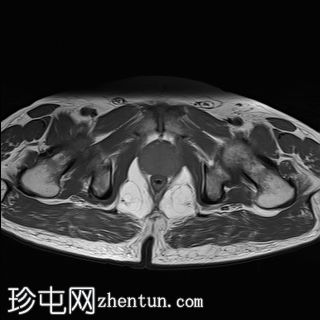

矢状位

T2加权像

外周带 (PZ):

T2WI:双侧外周带弥漫性、不均匀低T2信号,范围>15 mm,尖端后内侧可见小片相对保留的病灶。左侧尖端及腺体中部可见包膜隆起。评分5/5。

DWI/ADC:高b值DWI呈弥漫性高信号,ADC呈相应低信号(扩散受限)。评分5/5。

DCE:早期强化阳性。

PI-RADS:5 - 极高风险(极有可能存在临床意义的癌症),考虑炎症性病变。

肉芽肿性前列腺炎是多参数磁共振成像 (mpMRI) 中一种重要的、与临床意义显著的前列腺癌相似的疾病,因为它可以产生明显的周围带异常,伴有扩散受限和早期强化,通常导致较高的 PI-RADS 分级。

在本病例中,mpMRI 显示双侧周围带弥漫性 T2 低信号,高 b 值 DWI/ADC 图像上呈扩散受限,早期强化阳性,并伴有包膜轮廓隆起。这种影像学表现可能类似于浸润性或广泛性周围带癌,尤其是在 PSA 升高和直肠指检异常的情况下。然而,炎症性疾病,特别是肉芽肿性前列腺炎,可能出现类似的影像学表现。经直肠前列腺活检的组织病理学检查显示,患者患有严重的慢性非干酪性肉芽肿性前列腺炎,未见肿瘤证据。